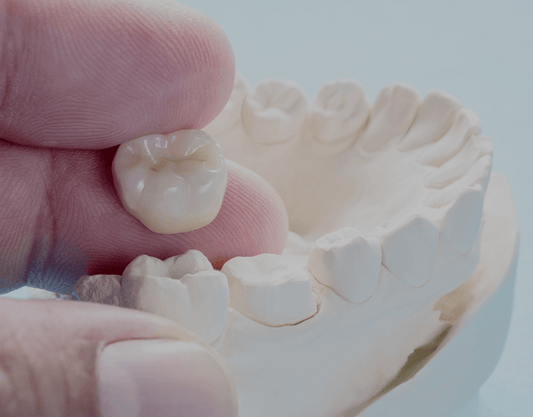

A dental crown is a restoration that covers the entire visible part of a tooth, and requires significant labor to create. They're used for a variety of reasons, like restoring a broken or damaged tooth, covering a discolored one, or even holding a dental bridge in place.

Before you receive a permanent dental crown, however, you will likely meet with your dentist at least once prior. After x-raying your tooth and preparing it to hold the crown, your dentist will make an impression of your teeth.

While a crown – shaped to fit your mouth perfectly – is being made from the mold, your tooth needs to be protected. The dentist will apply a temporary crown as a placeholder, meant only to protect the tooth until the permanent replacement arrives.

The cost of a dental crown can also vary depending on the type. There are several different types of materials used to create permanent crowns, and each has its own advantages and disadvantages. Some of these materials include:

Ceramic: All-ceramic dental crowns are made entirely out of porcelain and can be difficult to tell apart from authentic teeth. When it comes to metal crowns vs porcelain dental crowns, metal crowns are considerably stronger and more durable than porcelain.

Porcelain/metal: Porcelain-fused-to-metal (PFM) dental crowns combine metal with a porcelain coating for strength and are one of the most popular types of crowns. They’re usually less expensive than all-porcelain crowns and can be matched to your other teeth for a natural look.

Zirconia: These crowns are made from zirconium oxide, an extremely strong material that is both stain-resistant and aesthetically pleasing. Like all ceramic crowns, they can be matched to the color of your other teeth.